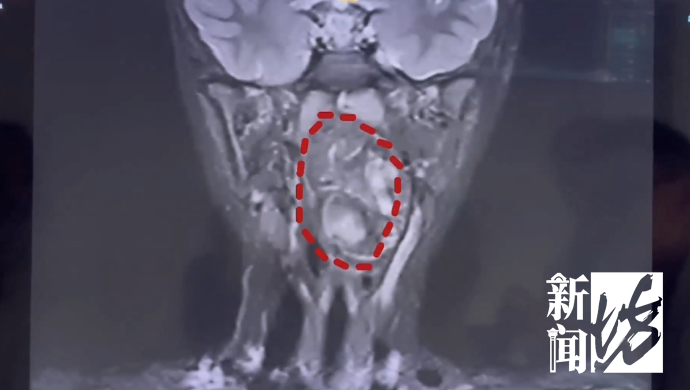

复旦大学附属儿科医院 耳鼻咽喉头颈外科副主任 陈超:我们可以看出它有脂肪,有软骨,这是一对双胞胎,一个是我们正常的人发育成的人,另外一个他可能残留在这个咽旁间隙里面,就发育成了这样的一个畸胎瘤。

医生解释,虽然畸胎瘤绝大多数是良性,但多生于腹腔内。像这样长在儿童咽喉部,而且又这么大的,极其罕见。肿瘤还在长大,如不及时干预,孩子恐有生命危险。

复旦大学附属儿科医院 耳鼻咽喉头颈外科副主任 陈超:6岁男孩的口咽腔大概在8公分左右,这个孩子的肿瘤已经高达6公分多,整个气道已经完全被这个膨大的肿瘤占据了,只有一条黑颜色的线,这是它透气的空间,再让它继续膨胀下来,它首先出现的一个症状应该是呼吸道的梗阻窒息,会出现窒息致死的可能。